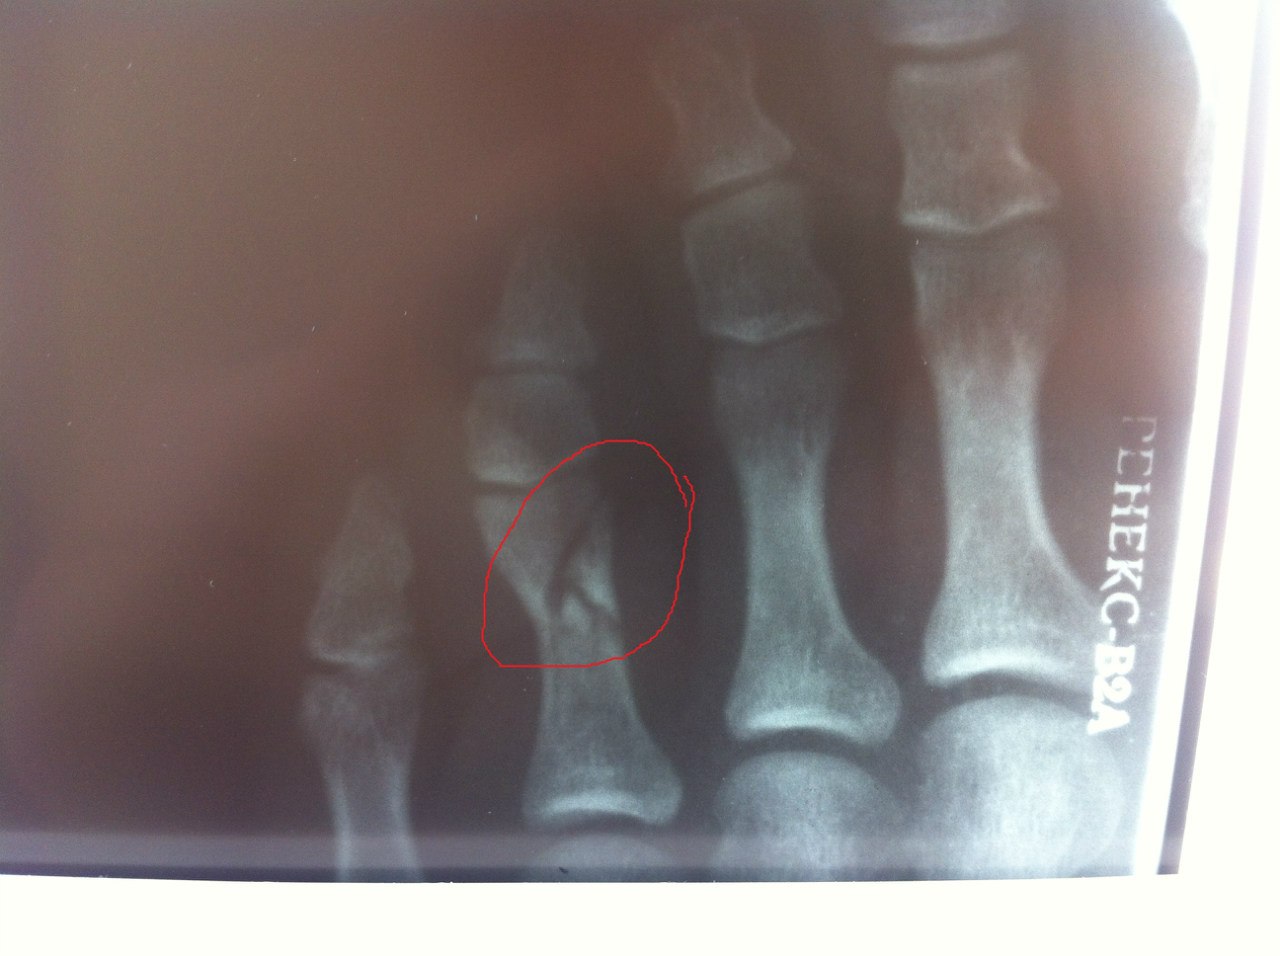

Клиническая картина перелома может напоминать вывих пальца, поэтому для дифференцирования необходимо провести рентгенологическое исследование. По назначению специалиста оно может осуществляться в двух проекциях, благодаря чему можно более точно визуализировать присутствующие повреждения, определяя их характер. Например, на рентгеновском снимке можно увидеть, произошло ли смещение отломков или нет.

Иногда даже рентгенография не позволяет точно установить диагноз, поскольку проявления перелома могут быть похожими на другие повреждения. Поэтому имеет смысл в проведении дополнительных инструментальных методов диагностики. Хотя обычно поставить правильный диагноз не составляет большого труда, особенно, если в диагностике принимает участие опытный травматолог.

После проведённого лечения обязательно проводится контрольная рентгенография, чтобы определить эффективность терапии, правильность расположения и сращения костей повреждённого пальца. При неправильном сращении возникает вероятность образования костной деформации, приводящей в итоге к ограничению движений конечности, на пальце которой произошёл перелом. Также повышается риск развития артроза, если речь идёт о внутрисуставных переломах. В будущем это патологическое состояние, имеющее хроническое течение, будет проявляться периодически возникающими болевыми ощущениями в пальце, нарушением функциональности нижней конечности.